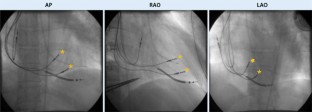

Die intermittierende Stimulationsabgabe erfolgt über 2 rechtsseptal transvenös platzierte Schraubelektroden, die mit der zusätzlichen Vorhofelektrode mit dem wiederaufladbaren Aggregat verbunden sind. Das Kontraktilitätsmodulationssystem verfügt weder über eine herkömmliche antibradykarde noch über eine antitachykarde Funktion.

Abb. 2